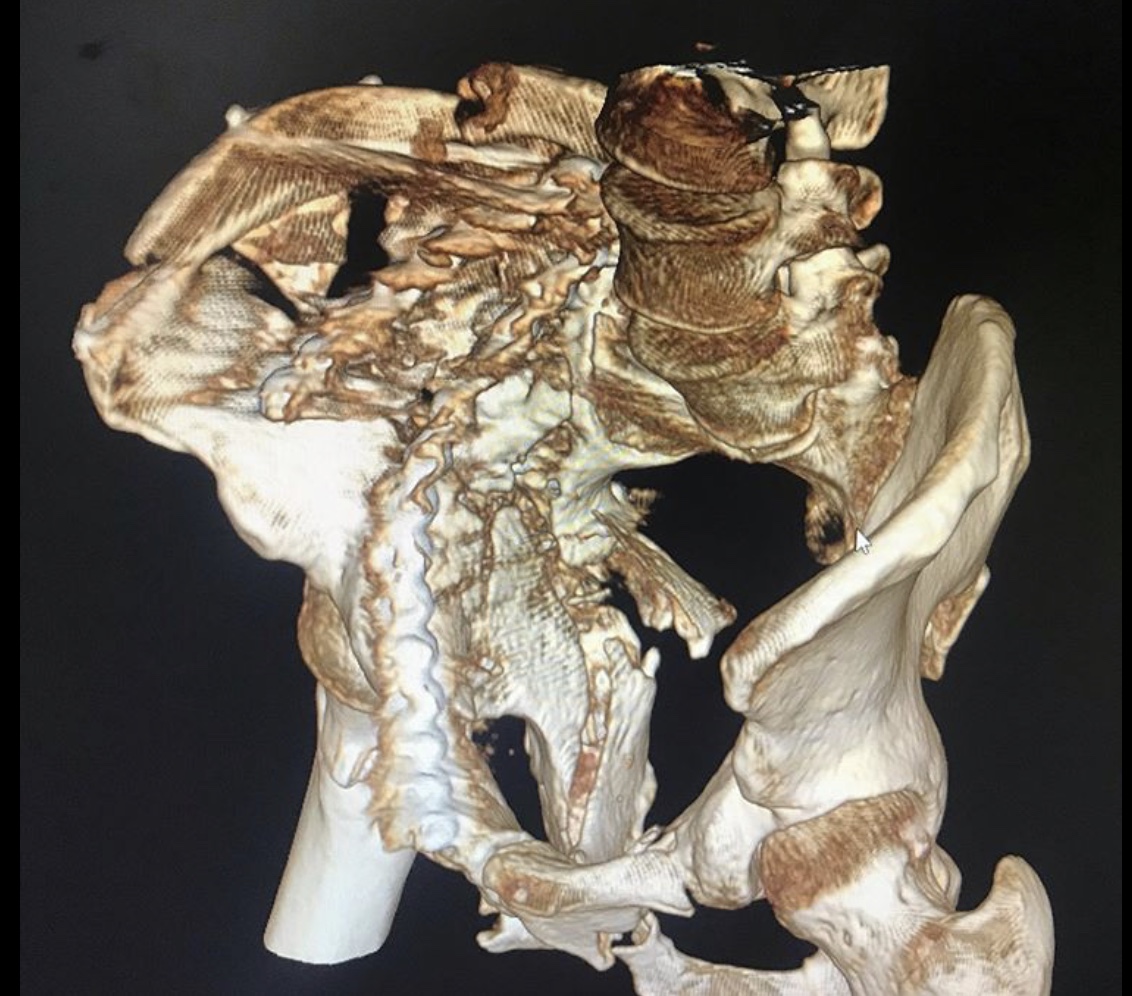

Перелом таза – тяжелейшая травма костей скелета, уступающая по опасности только травмам позвоночника и черепа. Она отличается особой опасностью, так как ее сопровождают обильная потеря крови и шока. Пострадавшему требуется экстренная врачебная помощь, иначе высок риск гибели. Даже при срочном врачебном вмешательстве не всегда удается спасти пострадавшего, который может погибнуть от кровопотери или осложнений болевого травматического шока.

Но к врачам-травматологам Городской клинической больницы № 7 Казани этот пациент поступил лишь спустя месяц после травмы. Врач – травматолог клиники Руслан Закиров признается: «Они в другом городе лечились. Жизнь спасали. К сожалению, не во всех больницах есть возможности для хирургии таза».

Пациента, что называется, «собрали».

Была выполнена открытая репозиция, остеосинтез пластинами.